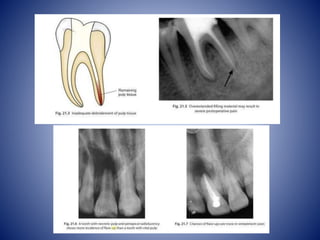

• Mechanical cause

 overinstrumentation of root

canal

 extrusion of root canal

filling materials

 incorrectly measured

working length

 Inadequate removal of

pulpal tissue

• Chemical causes

 Irrigation solutions

 Intracanal medicaments

 over extended Root fillings

• Incomplete removal of pulp tissues during the intial

appointment-

• In some instances due to lack of time factor the endodontic

therapy may consist of incomplete pulpectomy after a

diagnosis of acute or chronic pulpitis. This situation generally

occurs when the radicular pulp is already inflamed.